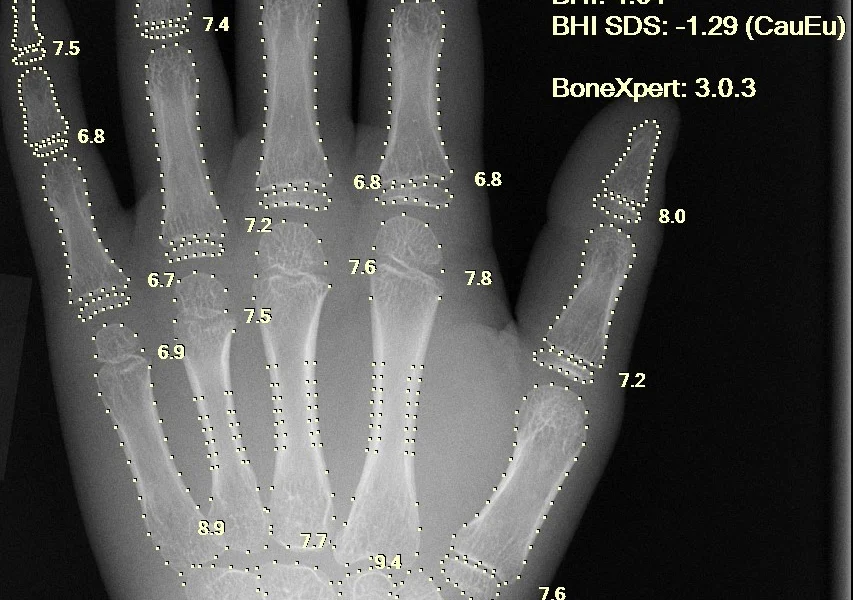

Viena iš pagrindinių DI funkcijų sveikatos sektoriuje yra ankstyvas ligų nustatymas. Algoritmai gali analizuoti medicininius vaizdus ir aptikti anomalijas, kurios gali būti ankstyvais ligos požymiais, tokiu būdu suteikiant galimybę pradėti gydymą anksčiau ir efektyviau. Be to, DI gali padėti personalizuoti gydymo planus, atsižvelgiant į individualius paciento poreikius ir sveikatos istoriją.